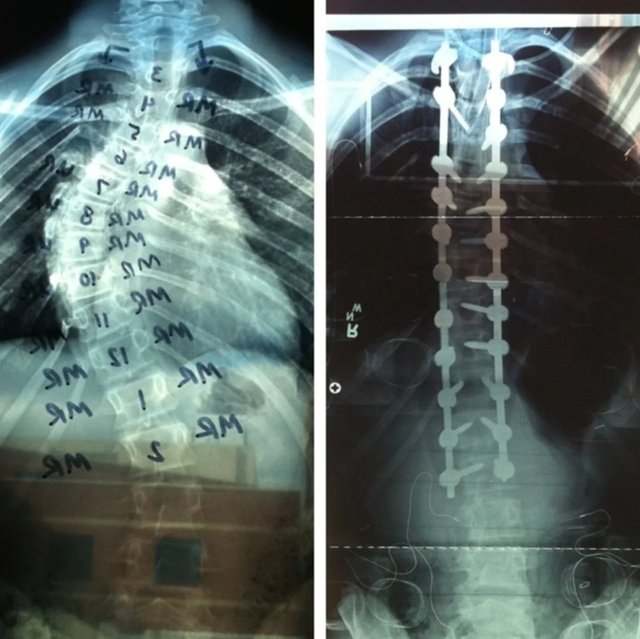

“Küçük kardeşim omurgasından yeni ameliyat oldu. İşte bazı röntgen öncesi/sonrası fotoğrafları.”